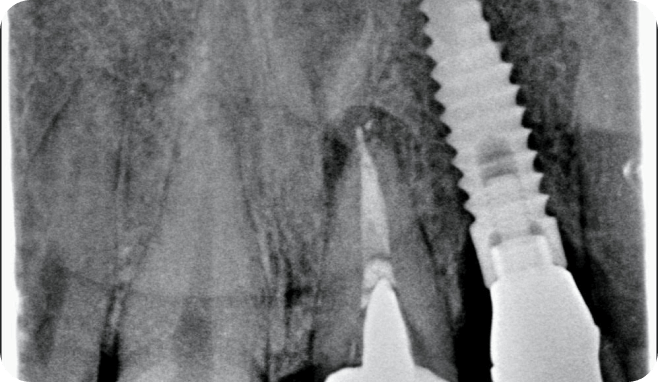

Casos

Instalaciones oral group Instalaciones oral group Instalaciones oral group Instalaciones oral group Instalaciones oral group Instalaciones oral group Instalaciones oral group